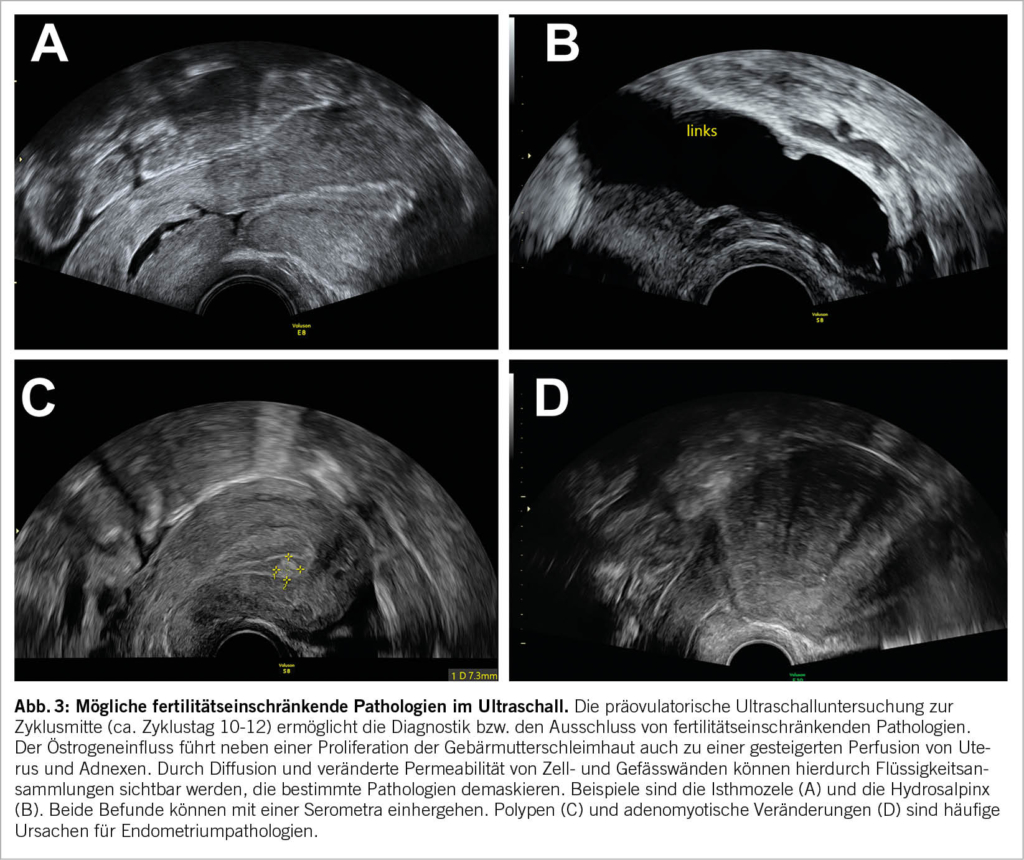

Die Patientin wird gebeten, sich bei Menstruationsbeginn zu melden, um zwischen Zyklustag 2-5 einen Untersuchungstermin zu erhalten. Bei dieser Untersuchung am Zyklusanfang sollten die Antralfollikel im Ovar gleichmässig gross (ca. 2-8 mm) und das Endometrium schmal sein (Abb. 1A1 & Abb. 1A2). Durch das einfache Zählen der vorhandenen Eibläschen in den Ovarien lässt sich der sogenannte «antral follicle count (AFC)» (Abb. 2A) erheben, der nachgewiesenermassen gut mit dem Anti-Müller-Hormon (AMH) korreliert und so eine verlässliche Aussage über die vorhandene Eizellreserve der Patientin zulässt (7). Je nach Alter existieren unterschiedliche Normalwerte für den AFC, die an Perzentilenkurven in der Literatur abgelesen werden können (8). Frauen mit polyzystischem Ovarsyndrom (PCOS) haben in der Regel eine ausserordentlich hohe Eizellreserve, die sich typischerweise in einer polyzystischen Ovarmorphologie (PCOM) manifestiert. Die zahlreichen und verhältnismässig kleinen Antralfollikel können hier in den Ovarien «perlschnurartig» angeordnet sein (Abb. 2B) (9). An dieser Stelle ist es wichtig zu erwähnen, dass die perlschnurartige Anordnung nach den Rotterdam-Kriterien kein sonographisches Diagnosekriterium für das PCOS ist. Massgeblich ist die Anzahl der frühzyklisch bestimmten Antralfollikel (mind. 20 pro Ovar) und/oder des Ovarvolumens (mind. 10 ml) (10).